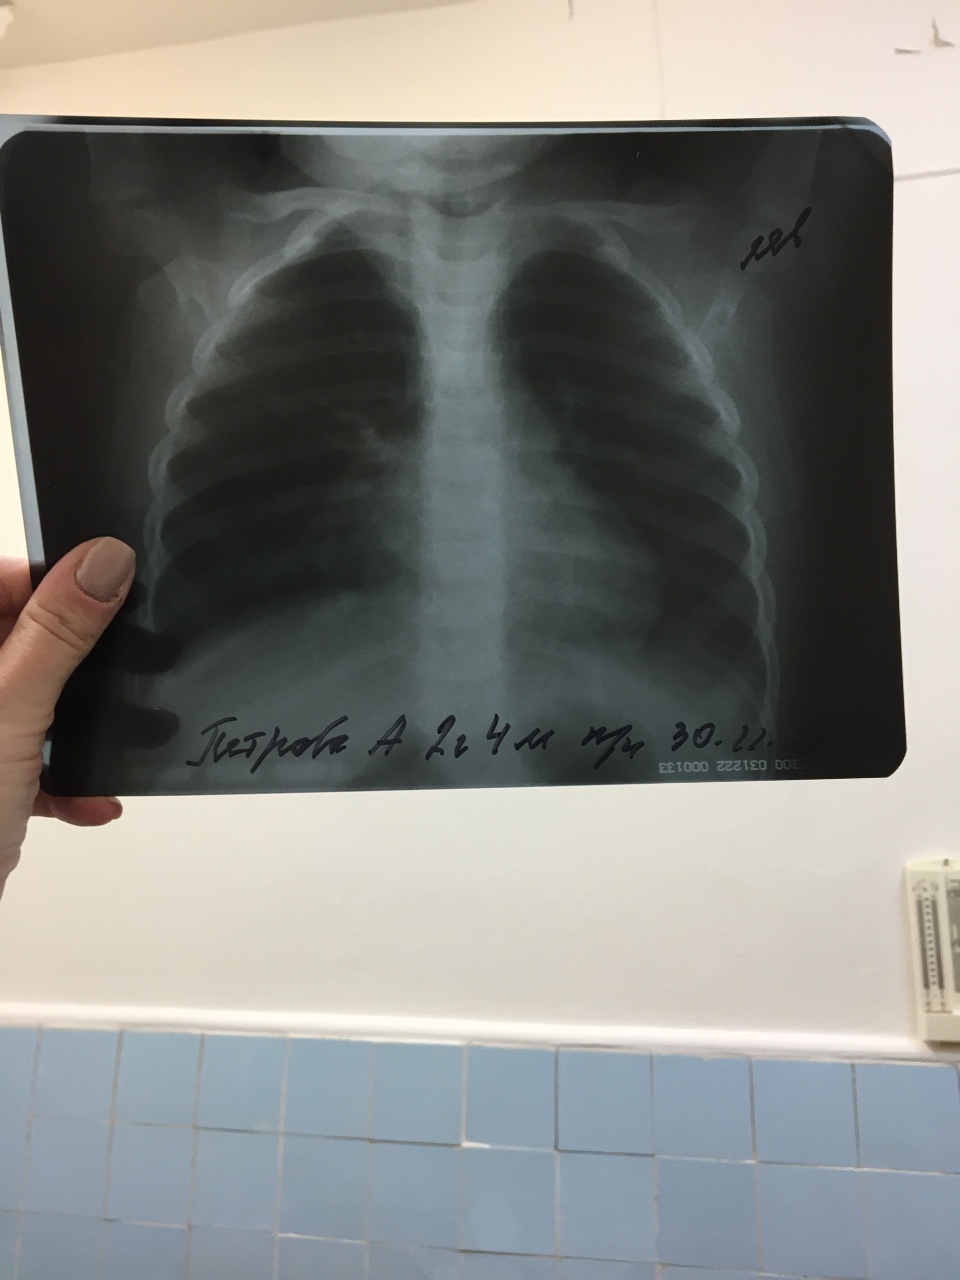

Рентгеновские технологии: усиленные экраны 35x35

Раздел: Фотопутеводитель